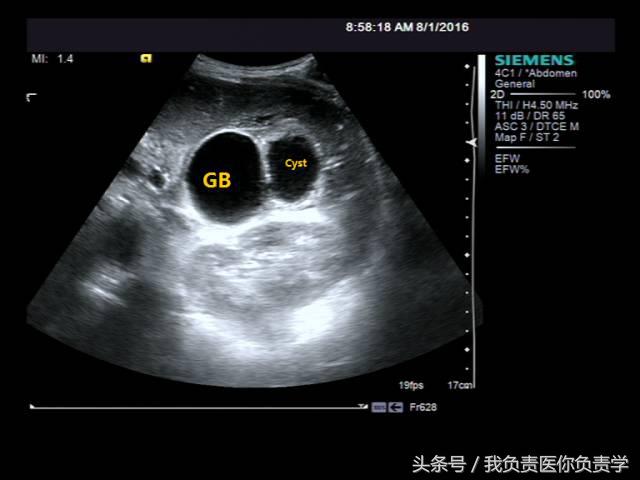

患者男,64岁,因右上腹疼痛半月余就诊。查体发现右上腹部轻压痛,无发热。超声检查所见如下:

图3示胆囊与囊性回声区间隐约可见裂隙相通